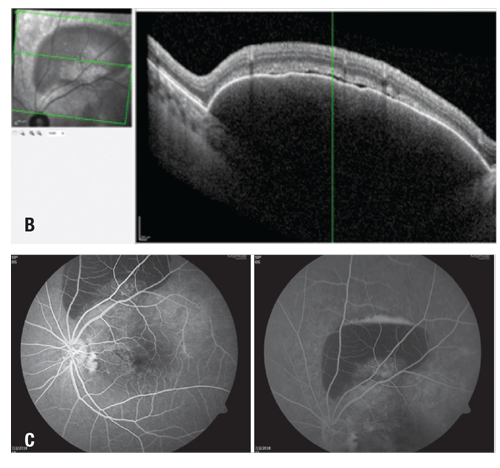

| Figure 2. Progression of optical coherence tomography raster scans through the fovea at (A) presentation before treatment in our clinic; (B) one month after presentation and after one injection of bevacizumab; (C) four months after presentation, after three bevacizumab and one aflibercept injections; and (D) 12 months after the initial visit, after three bevacizumab and fi veaflobercept injections and one photodynamic therapy session. Thirteen months after presentation and an additional aflibercept injection, the most recent image (E) showed flattening of the shallow pigment epithelial detachment central macula, and resolution of the subretinal fluid. |

We treated the hemorrhage and macular fluid with additional intravitreal bevacizumab injections. One month after the first injection, the subretinal hemorrhage displaced inferiorly just nasal to the fovea. She had three more monthly bevacizumab injections with near resolution of the subretinal hemorrhage, then we switched to intravitreal aflibercept (Eylea, Regeneron). With ongoing treatments, the patient achieved excellent anatomic recovery with flattening of the macular PED and stable visual acuity (Figure 2A to D).

After her third monthly aflibercept injection, the patient was lost to follow-up for seven weeks. She returned with enlargement of the PED in the central macula and an enlarged hemorrhagic PED along the superior arcade of the left eye (Figure 3A). Her visual acuity had decreased to 20/50.

At this point, we restarted aflibercept on a monthly basis, resulting in improvement of the macular PED, but with persistence of the PED along the superior arcade. We also prescribed oral eplerenone up to 50 mg daily for four months, but ultimately discontinued the medication because it did not appear to be helpful.

One month later, we treated the PED along the superior arcade with PDT followed by an aflibercept injection. The combination resulted in flattening of the shallow PED in the central macula (Figure 2D). Her visual acuity recovered to 20/30 in the left eye. The PED along the superior arcade persisted, but ultimately decreased in size